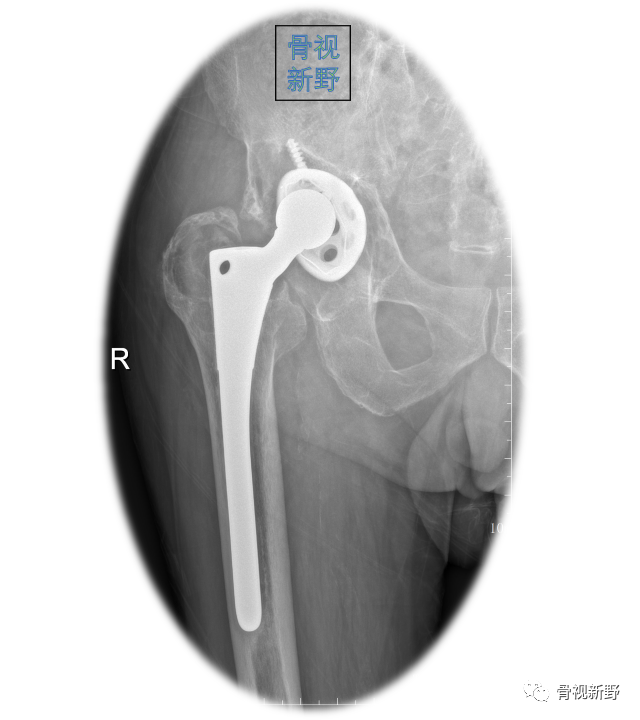

Case 3: Paprosky IIIa

Case 4:Paprosky IIIb